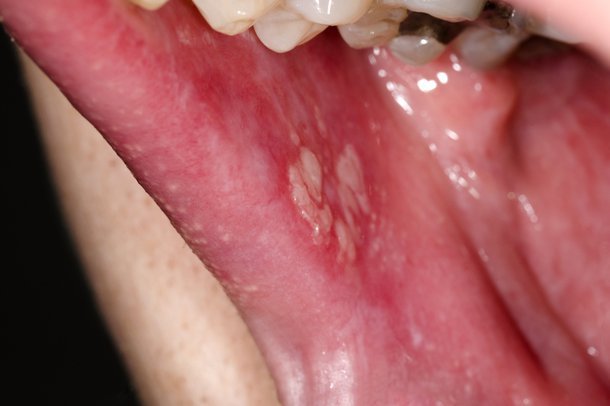

lichen planus - describe lesions

purple, pruritic, planar papules with white lacy markings on the surface of lesions

50% have mucosal involvement - mouth is most common

wickhams striae

what can exacerbate mouth lesions

spicy food